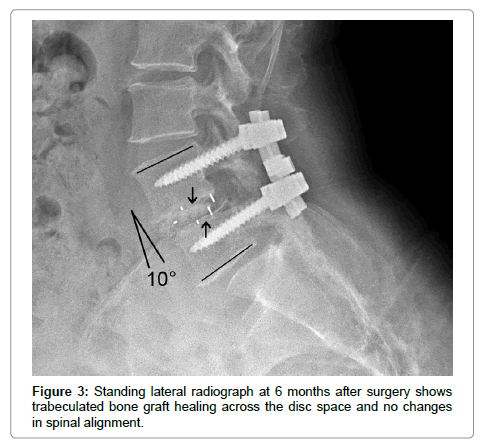

All patients showed radiographic evidence of fusion at 6 months after surgery; no patient showed motion across the fused interspace on dynamic flexion-extension lateral radiographs. No patient had lucency around the implant. There was no evidence of implant migration or hardware failure on postoperative radiographs in any patient throughout the duration of the study.

Postoperatively, the average disc space height was increased by 6 mm after surgery (Figures 1 and 2). The sagittal plane alignment was improved in all patients at surgery and was maintained at 12 months (Figure 3). The average preoperative sagittal plane angulation was -1° (lordosis) and ranged from +4° (kyphosis) to –3° (lordosis). Average sagittal plane angulation improved to an average of –7° (0° to –9° lordosis).